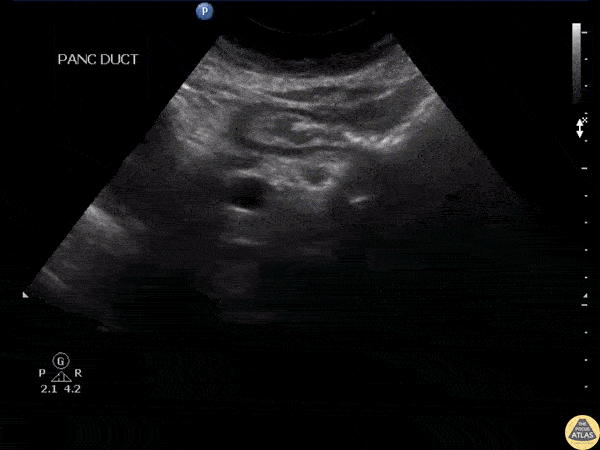

RUQ evaluation of a patient with chronic pancreatitis revealed pancreatic stones visible as hyperechoic structures within the pancreatic duct. Image courtesy of Robert Jones DO, FACEP @RJonesSonoEM Director, Emergency Ultrasound; MetroHealth Medical Center; Professor, Case Western Reserve Medical School, Cleveland, OH View his original post here